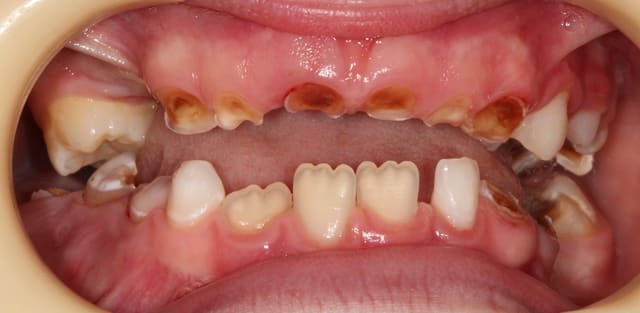

A 7 ans, cette demoiselle a eu une AG avec extractions de 14 dents temporaires.

A 10 ans, coca et chips à volonté, voici ses 11/21. Les 6 sont dans un état similaire.